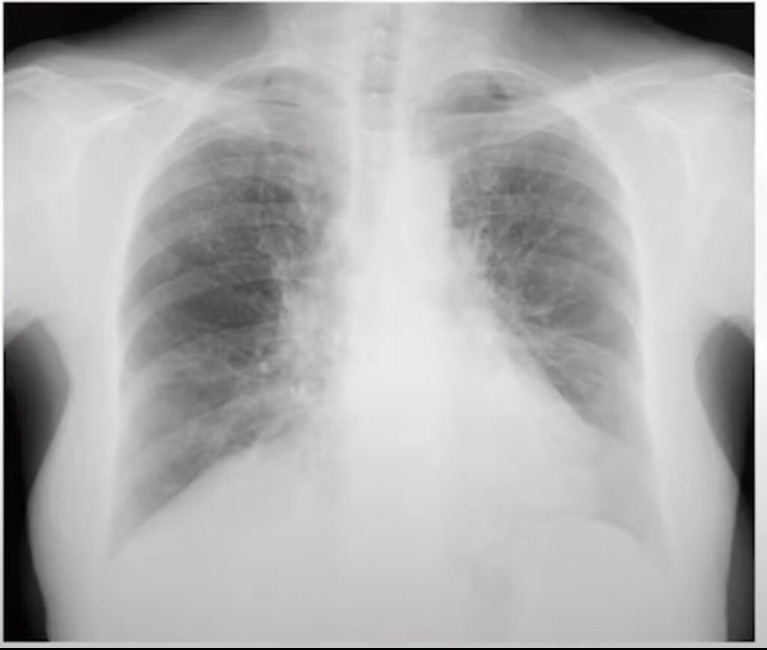

Azt mindenki tudja, hogy aki rosszindulatú daganatos megbetegedésben szenved, nagy az esélye annak, hogy hónapok, évek múlva már nem fog élni. De van még egy kór, amely több áldozatot követel, mint a rák, és amelynek tünetei 5 évvel bekövetkezte előtt megjelennek, így figyelmeztetve az illetőt a veszélyre....